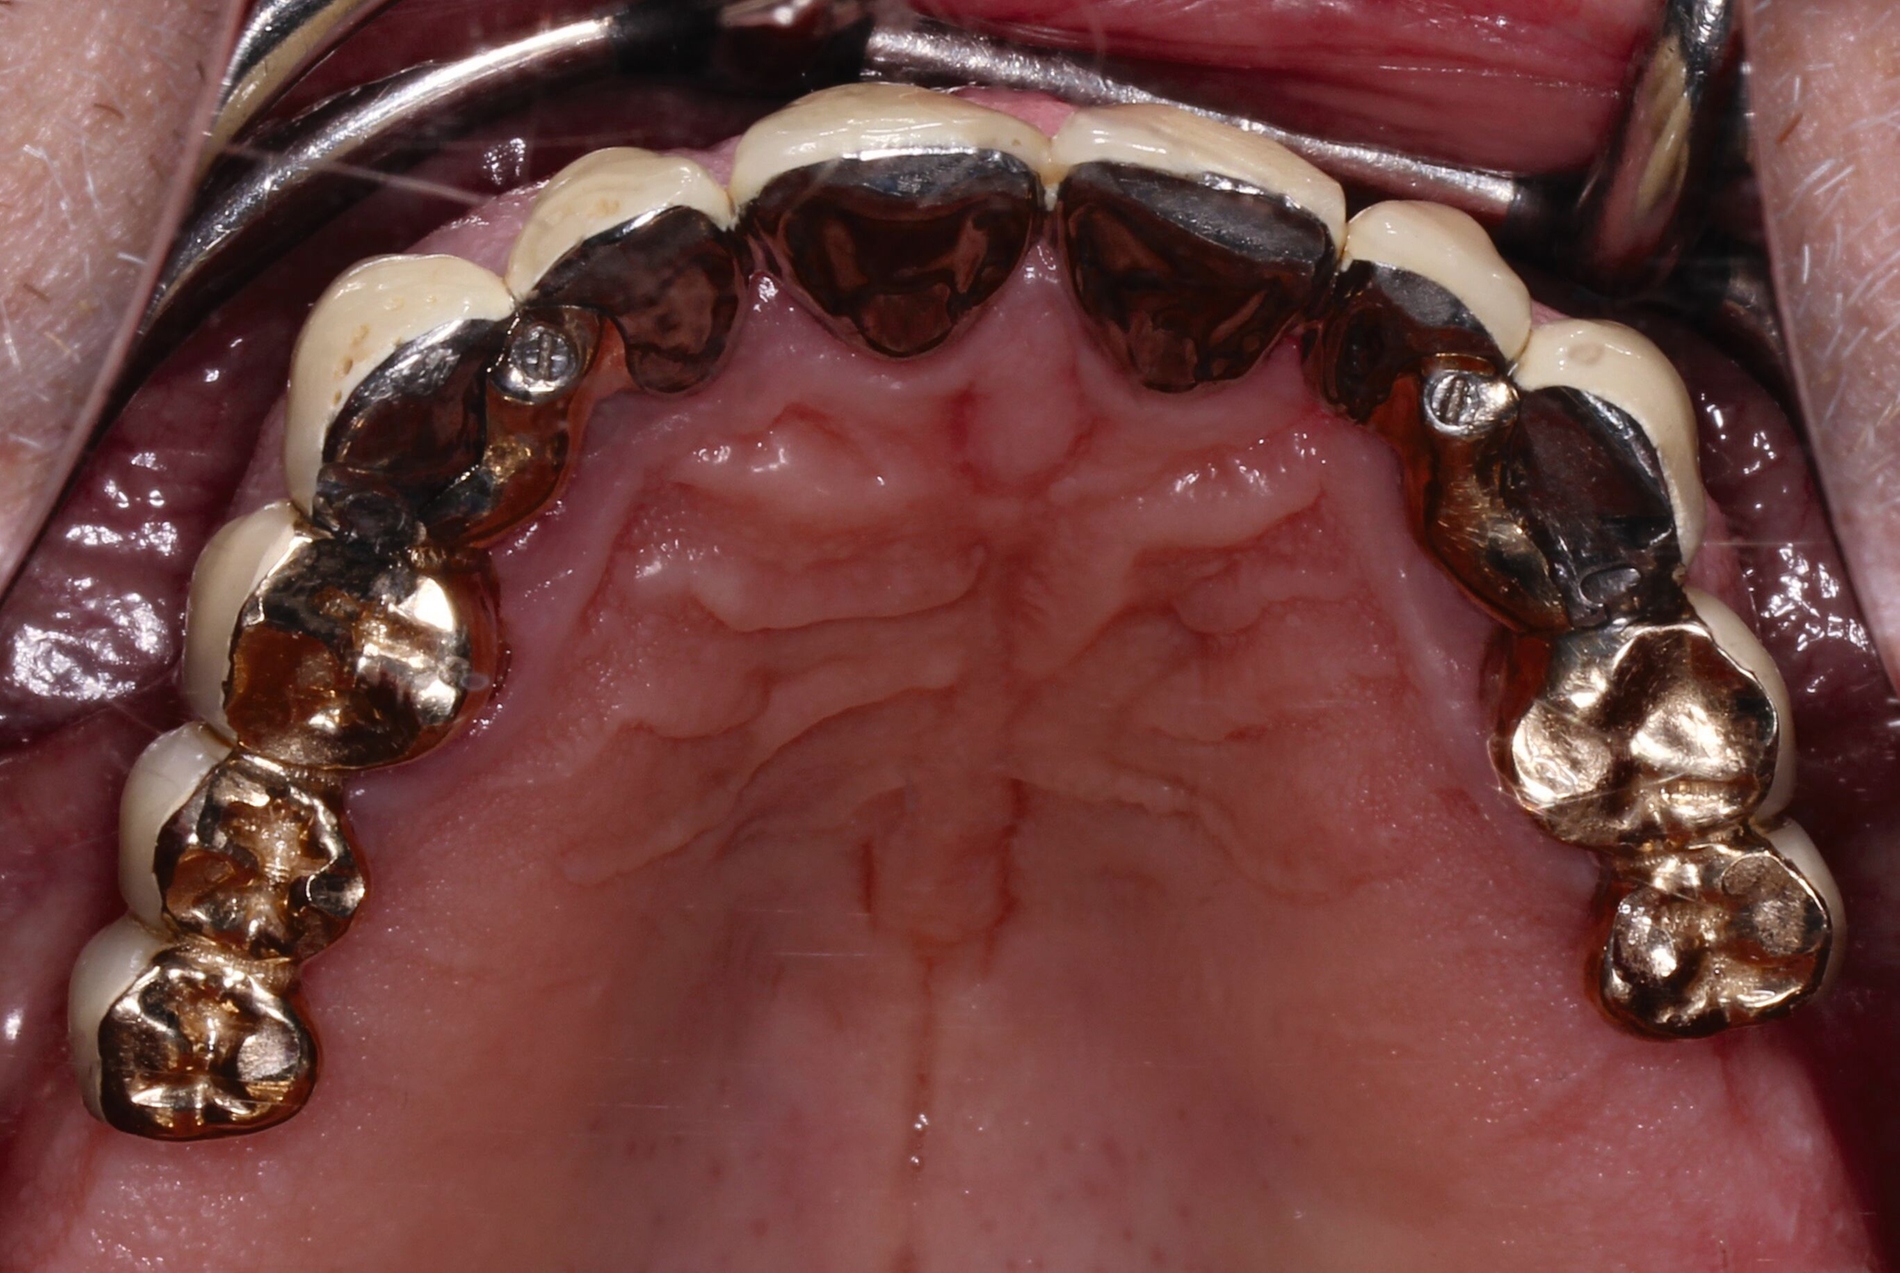

Der Patient stand unter der Dauermedikation von Metformin 500 mg, Ramipril 5 mg, Torasemid 10 mg, Metohexal 47,5 mg, Simvastatin 20 mg, Tamsulosin 0,4 mg und 3 mg Marcumar (INR 2,5–2,8) bei Zustand nach einer Bypass-Operation im Jahr 2019. Klinisch zeigten sich im Oberkiefer insuffiziente, verblockte und verblendete NEM-Kronen mit beidseitigen Gold-Extensionen distal, die über Geschiebe mit dem anterioren Anteil verschraubt waren (Abbildungen 1 und 2). Der Patient berichtete, dass die vorhandenen Kronen und Brücken 1984 eingesetzt worden seien.

Besonders auffällig war eine Dezementierung, die klinisch durch rechtsseitigen Druck und Zug mit einer Pinzette und daraufhin austretende Sulkusflüssigkeit in Regio 14 detektiert wurde. Da entsprechend des synoptischen Behandlungskonzepts [Naumann et al., 2010] bei prothetischer Neuversorgung eine gesamte Evaluation der Restpfeiler erfolgen muss, wurden zunächst die Kronen im Oberkiefer durch Schlitzen und Aufbiegen entfernt. Erst danach ließ sich deren Erhaltungswürdigkeit abschließend beurteilen.

So war der Zahn 14 tief kariös zerstört und nicht-erhaltungswürdig, was mit dem Bild der wahrscheinlich seit Längerem bestehenden Dezementierung korrelierte (Abbildung 3). Die Brücken im Unterkiefer wurden als suffizient befundet. Die Ruheschwebelage wurde mithilfe des Zielinsky-Zirkels auf 2 mm bestimmt. Parodontologisch zeigten sich stabile Verhältnisse. Ein Parodontaler Screening-Index (PSI) wurde erhoben (3-1-1-1-2-2). Der hier auffällige Zahn 14 wurde bereits zuvor beim klinischen Befund als nicht-erhaltungswürdig eingestuft und im Verlauf extrahiert.